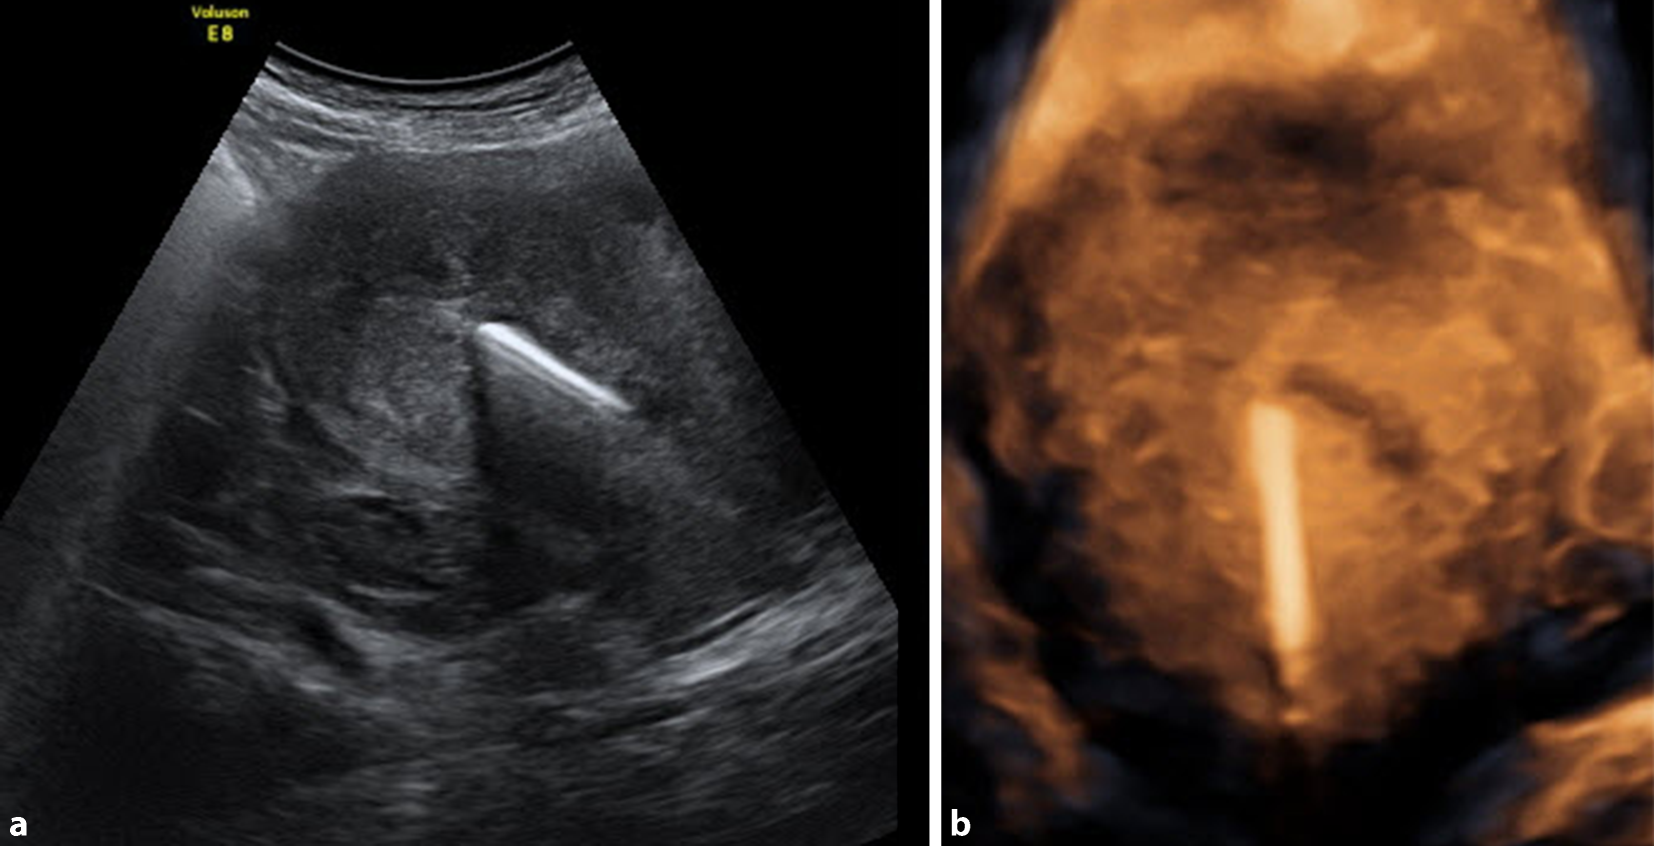

Spiralen sind unsere besten Freunde

Wer im gynäkologischen Ultraschall (abdominal wie vaginal) noch unsicher ist, hat vor allem durch Kupfer-IUD eine große Hilfe bei der Orientierung [1]. Dies gilt auch für die Anwendung der 3‑D-Option von abdominal, wobei sich die Presets für das erste Schwangerschaftstrimenon bei den meisten Geräten als ideal erweisen (Abb. 3a, b).

Abb. 3

Nicht ganz im Fundus uteri lokalisierte Kupferspirale im B‑Mode-Schall (a) und im 3‑D-Schall (b), jeweils von abdominal